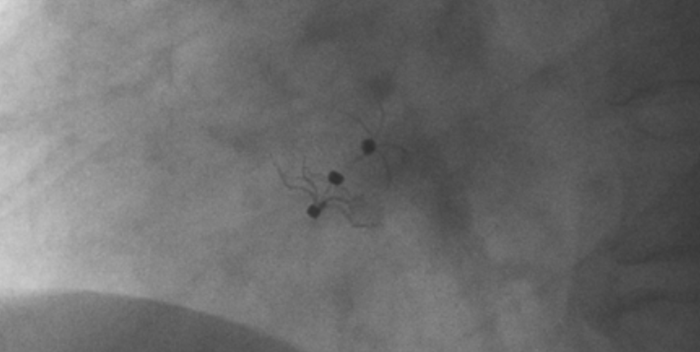

術中造影顯示患者為PFO且長隧道型,目前市場上已商業(yè)化的PFO封堵器難以滿足該患者解剖結(jié)構封堵需求。迪創(chuàng)醫(yī)療自主研發(fā)的OmniSeal PFO封堵器自適應性雙盤貼合設計能廣泛適應不同PFO隧道長度的解剖結(jié)構和形態(tài),其雙盤外包覆式阻流和隧道內(nèi)填充阻流相結(jié)合的雙重阻流設計,可為此患者實現(xiàn)有效封堵。與此同時,OmniSeal首創(chuàng)的完全可穿刺式設計,也為此患者最大程度地保留了房間隔區(qū)域穿刺通道,以實現(xiàn)全兼容未來可能的左心系統(tǒng)二次介入術。術終造影和心臟超聲顯示封堵完全、效果良好。作為OmniSeal的首例臨床應用,本次手術的順利完成和優(yōu)異效果充分體現(xiàn)了產(chǎn)品的設計創(chuàng)新優(yōu)勢。

影像顯示試驗器械適應性貼合于房間隔兩側(cè)且穩(wěn)定